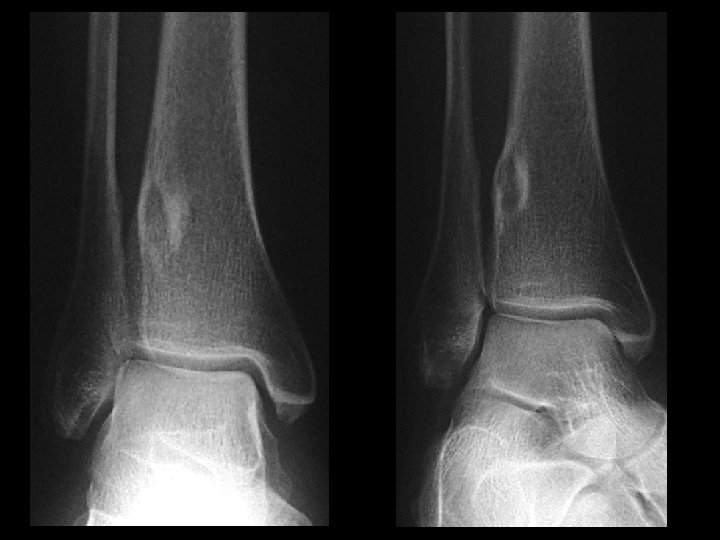

Talar osteochondral fracture • Findings: – Cortical irregularity of the lateral talar dome with bony fragments in the lateral mortise and widening of the distal tibiofibular syndesmosis – Check for proximal fibula fracture • ddx: – NONE! – This is an Aunt Minnie!